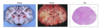

A perivascular cuff of inflammation surrounds the thickened ependymal lining of the ventricles and extend into the adjacent parenchyma. Just ventral to the dorsal portion of the lateral ventricle is a small granuloma (H&E stain).

What is shown in this subgross transverse section of a kitten brain, what is your top DD?

FIP